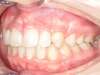

Encombrement aux deux arcades.Traitement par gouttières.

Avant

Après